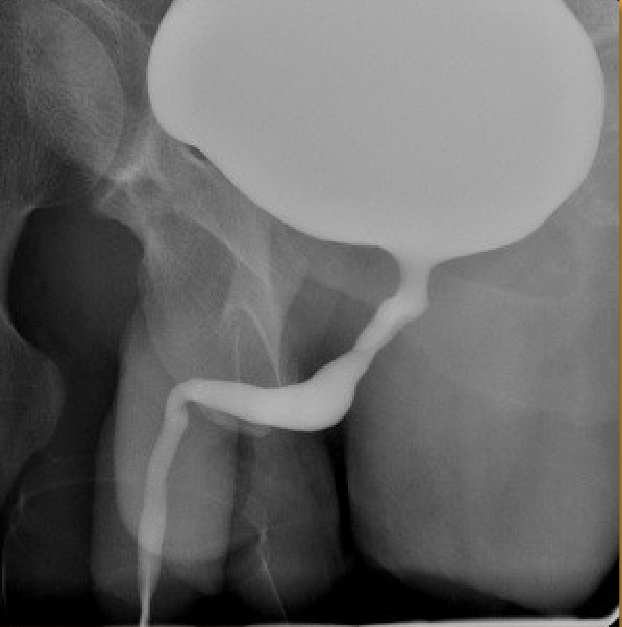

What contrast procedure was performed to produce this image?

VCUG – Voiding Cystourethrogram

NOT A cystography bc they are voiding in the image as shown by the line below of the urethra

1)procedure performed?

2)contrast media used?

3)How contrast media administered?

1)Cystogram (Retrograde Cystography)

2)Water-Soluble Iodinated Contrast

3)retrograde (tube through urethra)